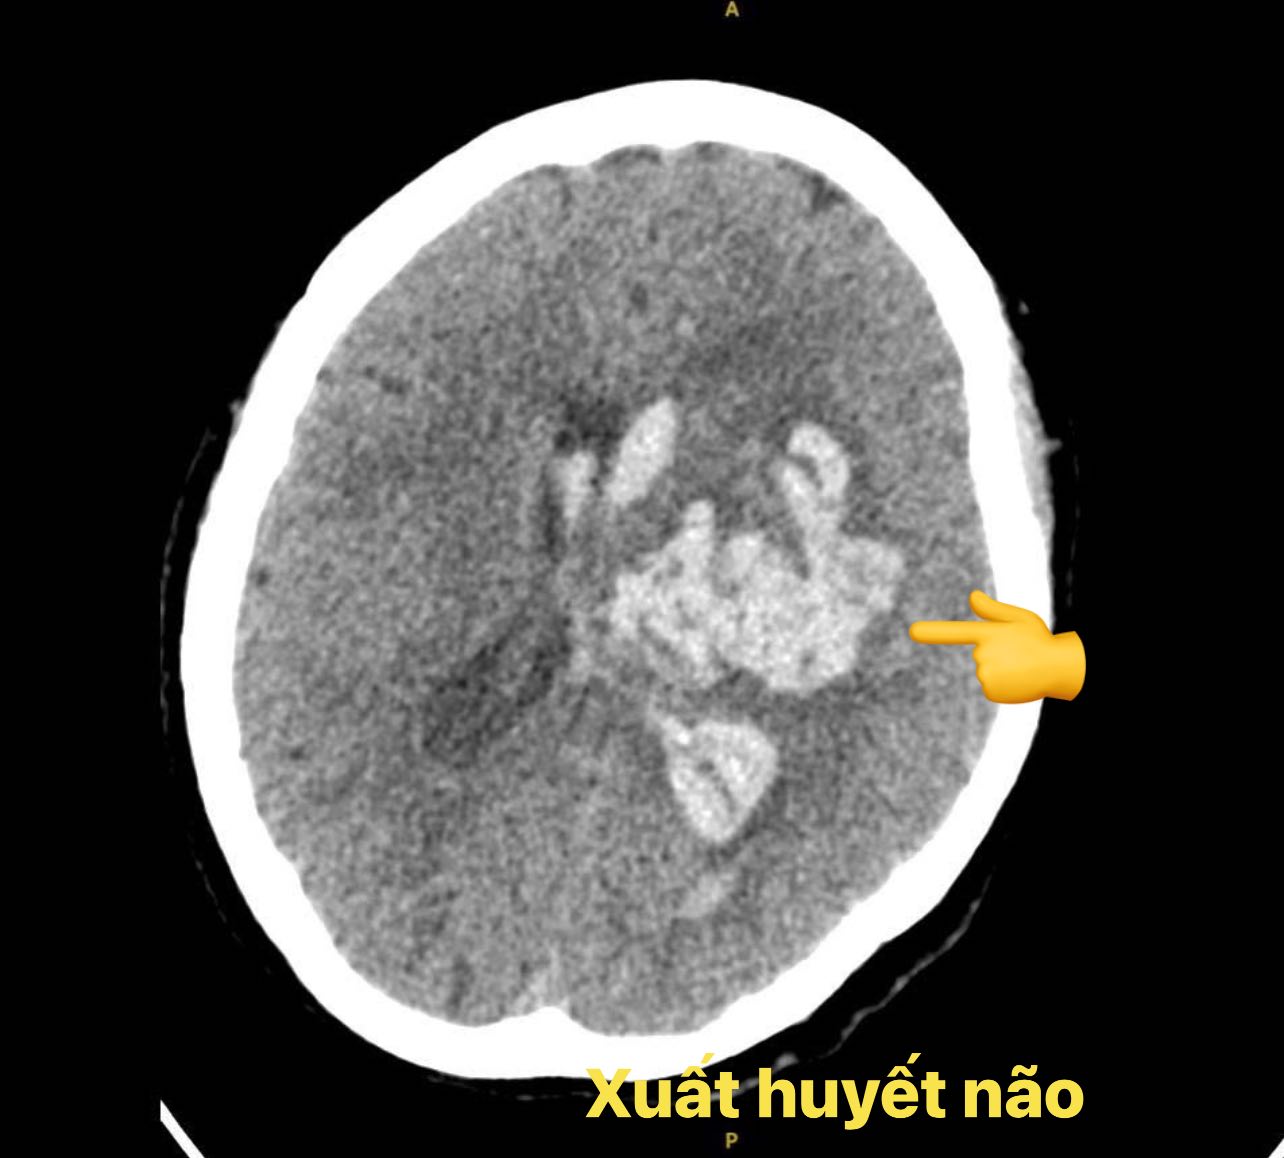

Bệnh nhân là nữ, 59 tuổi, có tiền sử tăng huyết áp và đái tháo đường nhưng uống thuốc không đều. Tối 10/8/2025, sau khi cãi vã và nổi giận với con, người bệnh đột ngột hôn mê. Gia đình đưa vào bệnh viện gần nhà, chụp CT sọ não cho thấy ổ xuất huyết não lớn, máu tràn vào não thất, gây chèn ép, lệch đường giữa, đe dọa tính mạng.